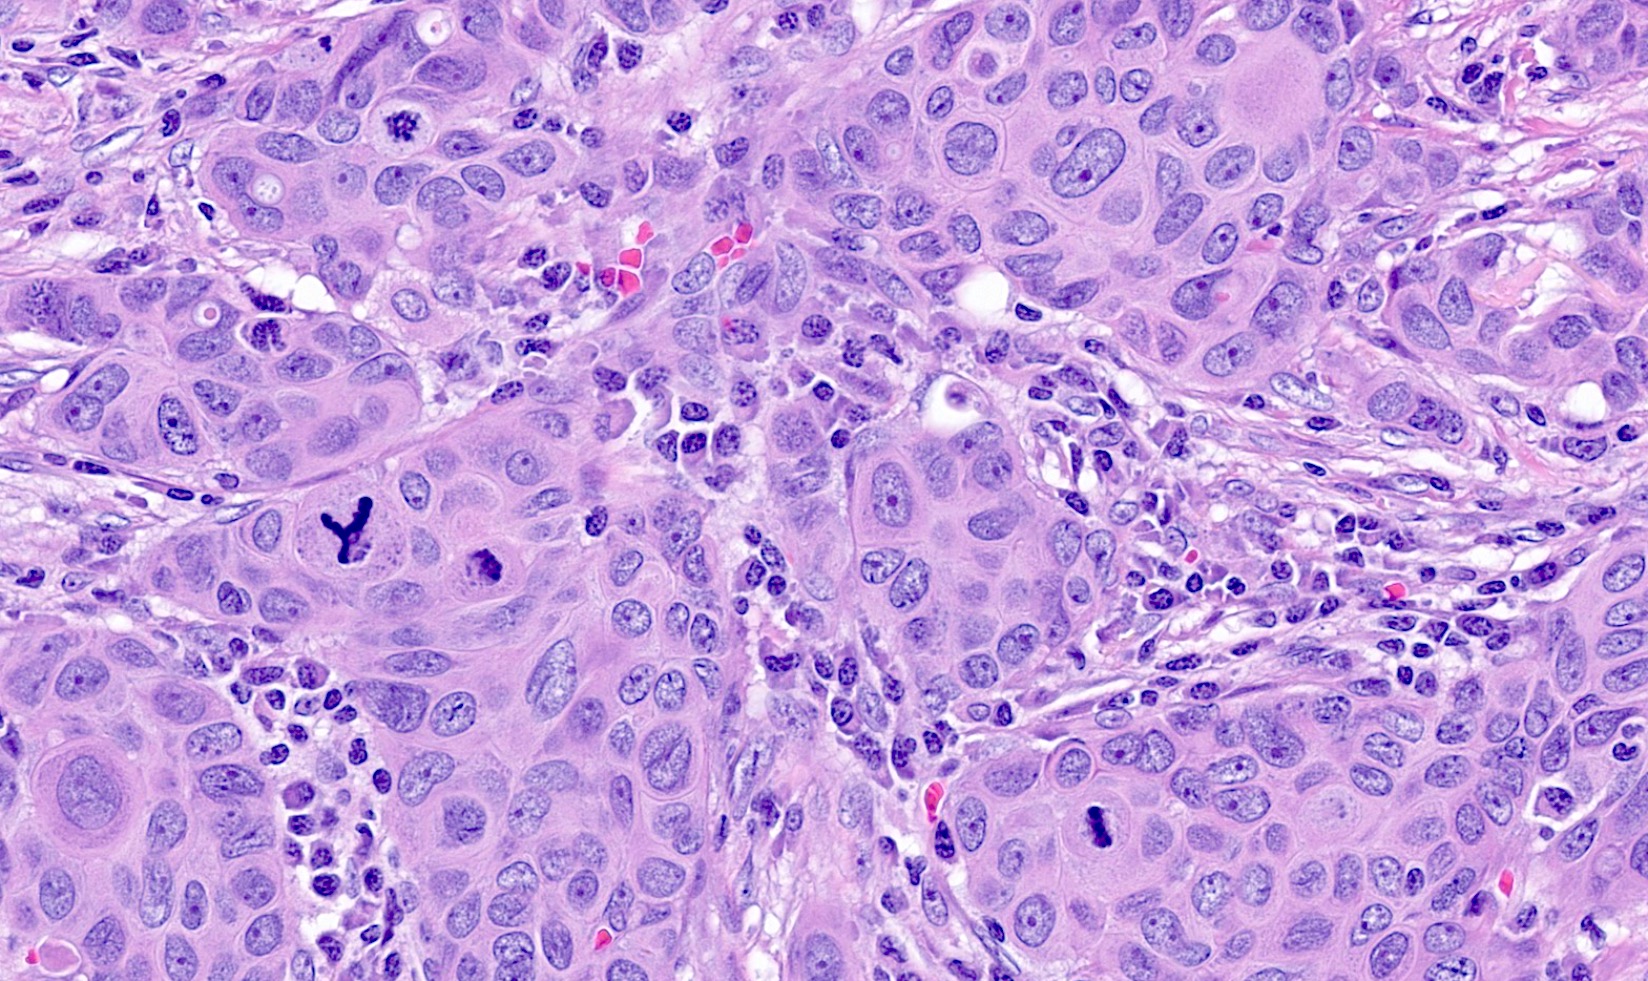

- Basal-like: high grade IDC, NST, solid tumor growth with pushing borders, geographic necrosis, nuclear pleomorphism, brisk inflammatory infiltrate, high mitotic index, high Ki67

- Predominantly IDC, NST of high histological grade

- Tumor cells frequently have pleomorphic nuclei and more abundant eosinophilic cytoplasm than triple negative cancers

- Ki67 proliferative rate is high (20 - 60%)

A 67 year old woman underwent a partial mastectomy for a breast tumor shown in the image. Microscopic sections revealed a high grade invasive ductal carcinoma growing as a solid mass with pushing borders, areas of necrosis, brisk mitoses and abundant tumor infiltrating lymphocytes. The tumor was negative for ER, PR and HER2 and was classified as basal-like by gene expression profiling. What other immunostain(s) might be positive?

B. EGFR. Basal-like breast cancers are typically high grade invasive ductal carcinoma of no special type that show solid tumor growth with pushing borders, geographic necrosis, nuclear pleomorphism, a brisk inflammatory infiltrate, a high mitotic index and a high proliferative index with Ki67. Most basal-like breast cancers express basal cytokeratins (keratin 5/6, 14, 17) and EGFR. Answer A is incorrect because while a minor proportion of triple negative breast cancers can express androgen receptor, the prototypical AR positive breast tumor has apocrine features (apocrine carcinoma). Answer C is incorrect because KIT is not characteristically expressed in breast carcinomas. Answer D is incorrect because synaptophysin may be expressed in breast tumors with neuroendocrine differentiation, which typically cluster within the luminal category.